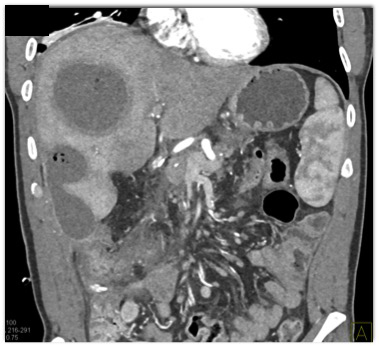

In this patient post Whipples procedure for pancreatic adenocarcinoma the best diagnosis is?

metastases to the liver

liver infarction

liver abscess

infected cyst